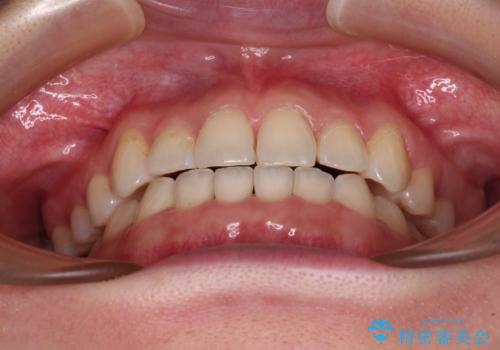

順調に後方移動することができ、わずか1年強で治療を終えることができました。

顎骨が小さいので第二大臼歯が欠損しても負担は少ないと思いますが、奥歯でもっとしっかりと咬みたいということであれば、インプラント補綴治療を4本分行うこととなります。